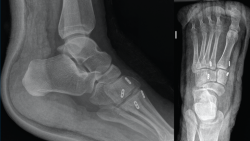

Figura 2. Caso 1. Resultados radiográficos posquirúrgicos.

Se realiza la intervención quirúrgica a las 8 semanas con reducción abierta mediante abordaje dorsomedial confirmando la inestabilidad articular y realizando una estabilización con sutura intraósea con botón de C1-M2. Se comprueba que aún persistía cierta inestabilidad en el plano frontal, por lo que se decide poner otro dispositivo de C2 a M1. Se inmoviliza con una férula suropédica y se indica descarga (Figura 2).

La revisión a los 3 meses mostró resultados satisfactorios en ambos casos, con tolerancia de la carga completa. Además, las imágenes radiológicas demostraron el mantenimiento de la reducción conseguida en el quirófano, sin movilización del material (Figuras 5 y 6).

Figura 5. Resultados radiográficos posquirúrgicos en el caso 1.